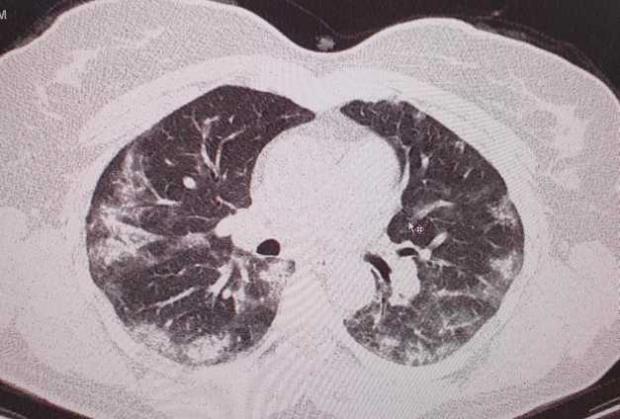

În postarea sa, medicul a arătat şi explicat modificările suferite de plămânii unei paciente confirmate cu Covid-19.

"Opacităţi "în sticla mată" dispuse la periferia plămânilor...foarte concludente...", a explicat dr. Alexandru Andriţoiu